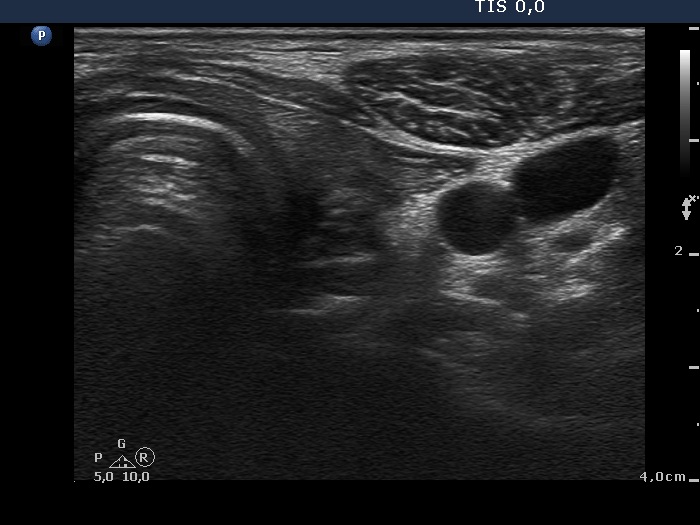

Examination before surgery (first row of images):

Clinical data: A 21-year-old woman requested a second opinion. She has been treated for Graves' hyperthyroidism for three years. The hyperthyroidism relapsed two times. She suffered from mild exophthalmos and occasionally diplopia. Actually, she had no complaints.

Palpation: The thyroid lobes were enlarged. There were no palpable nodules.

Result of blood test: subclinical hyperthyroidism on daily 15 mg methimazole therapy (TSH 0.001 mIU/L, FT4 12.9 pM/L, FT3 4.11 pM/L).

Ultrasonography. The thyroids were echonormal and contained hypoechogenic discrete areas none of them corresponded to a nodule. The echogenicity index was around 30%. The vascularization was average.Surgery was advised. Total thyroidectomy was performed. Histopathology disclosed diffuse goiter, focal lymphocytic thyroiditis.